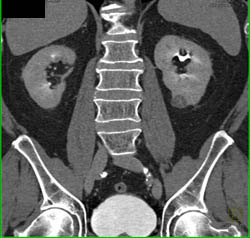

Complex Right Renal Cyst With Calcification